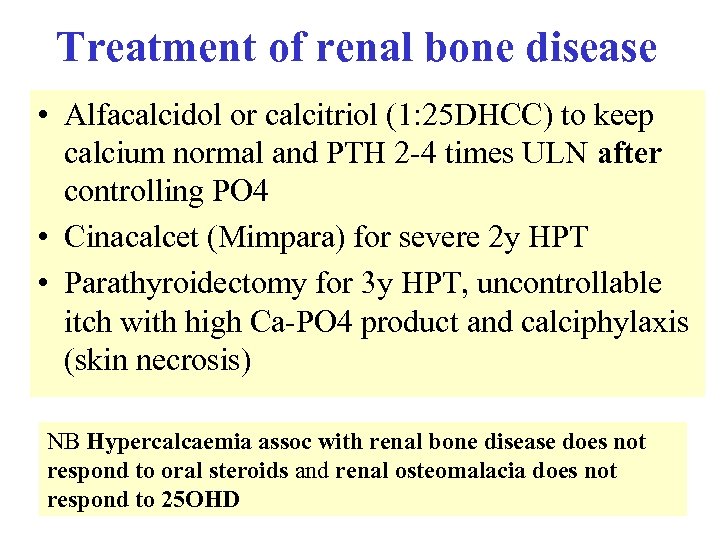

Treatment of renal bone disease • Alfacalcidol or calcitriol (1: 25 DHCC) to keep calcium normal and PTH 2 -4 times ULN after controlling PO 4 • Cinacalcet (Mimpara) for severe 2 y HPT • Parathyroidectomy for 3 y HPT, uncontrollable itch with high Ca-PO 4 product and calciphylaxis (skin necrosis) NB Hypercalcaemia assoc with renal bone disease does not respond to oral steroids and renal osteomalacia does not respond to 25 OHD

Treatment of renal bone disease • Alfacalcidol or calcitriol (1: 25 DHCC) to keep calcium normal and PTH 2 -4 times ULN after controlling PO 4 • Cinacalcet (Mimpara) for severe 2 y HPT • Parathyroidectomy for 3 y HPT, uncontrollable itch with high Ca-PO 4 product and calciphylaxis (skin necrosis) NB Hypercalcaemia assoc with renal bone disease does not respond to oral steroids and renal osteomalacia does not respond to 25 OHD